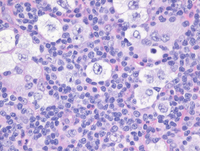

High power H&E images

At higher power, there are scattered large cells with clear cytoplasm and central nuclei present in a background of small lymphocytes. Further examination demonstrates that the large cells are either mononuclear or multinucleated variants of Hodgkin/Reed-Sternberg cells, also called "lacunar cells". Lacunar cells represent an artifact of formalin fixation due to retraction of the cell membrane as a result of formalin fixation.